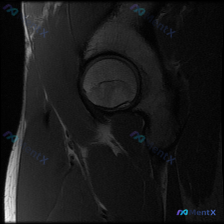

最近看到一份髋关节MRI分析的病例材料,有几个点值得讨论: 该影像为髋部MRI T1序列冠状位,报告提到股骨头内有典型的“新月征”(软骨下骨折线),提示缺血性坏死可能;同时也指出盂唇病变(撕裂/退变)的可能性。 问题1:仅凭这张T1序列,最应该优先考虑哪个诊断? 问题2:评估盂唇病变还需要完善哪些序...

最近看到一份单幅髋关节MRI T1加权冠状位图像的分析材料,用户的初始问题是关于“Labral pathology”(盂唇病变),但影像的核心客观发现似乎不太一致。先放分析内容里的关键信息,大家讨论一下: 影像表现: - 股骨头外形整体尚完整,前上方(负重区)皮质下见明显异常信号 - 股骨头、股骨颈...